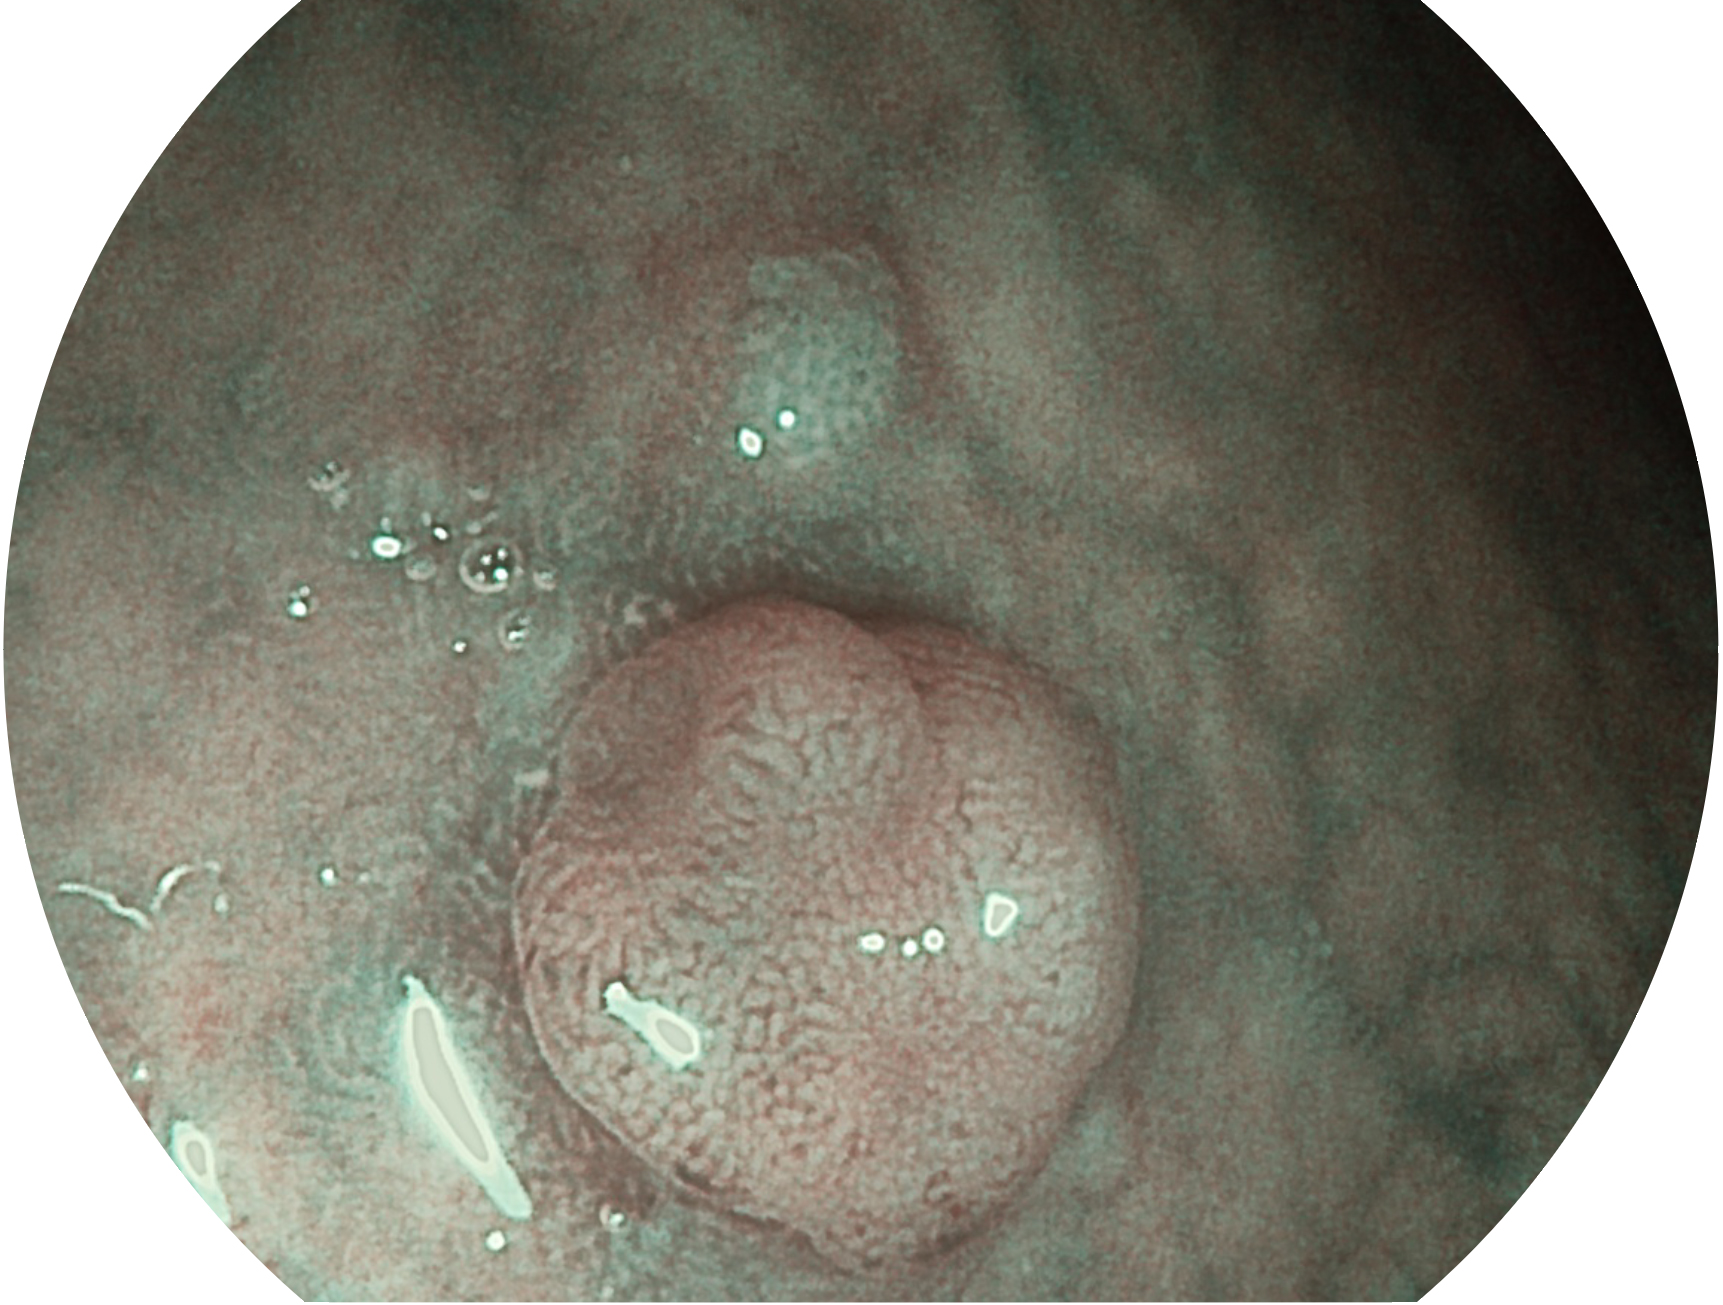

1xBET新开发的内镜染色技术,主要是基于多波长LED 光源的开发,VLS-55Q 四波长LED 光源是由四个不同颜色的LED光按照相应照明模式所规定的特定发光比例进行合束后形成,合束后形成的照明光的光谱由红光、绿光、蓝光及蓝紫光这四个不同的波段范围构成。具有更高光谱自由度,通过光谱比例的控制,实现了聚谱成像技术,英文全称为“Spectral Focused Imaging, SFI”,缩写为“SFI”和光电复合染色成像技术,英文全称为“Versatile Intelligent Staining Technology, VIST”,缩写为“VIST”。